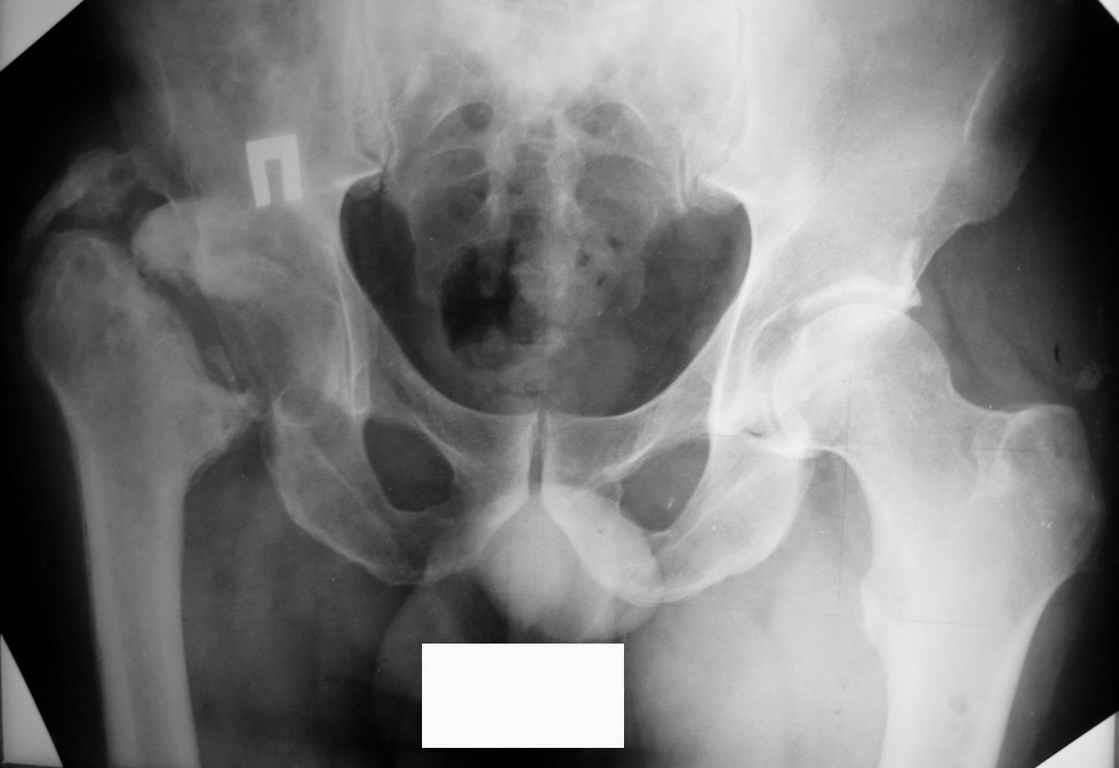

Был оперирован, среди прочего - остеосинтез DHS-фиксатором чреcшеечного перелома правого бедра, DCS-фиксатором остеосинтез оскольчатого чрезмыщелкового перелома левого бедра. Однако, в связи с развитием гнойного коксита были вынуждены убрать DHS-фиксатор и головку. Гнойный свищ правого тазобедренного сустава закрылся сразу после операции. Из-за вторичного смещения и поломки винтов пришлось удалить DCS-фиксатор и сращивать левое бедро внешней иммобилизацией. Прошло чуть более года. Пациент ходит с опорой на обе ноги,пользуется палочкой. Справа относительное укорочение 3см. Слева варус 33гр., тугой ложный сустав н/3бедра. Движения в коленных суставах почти в полном объёме.Перед нами встали вопросы, с чего начать? Протезирование правого ТБС? Восстановление опорности левой конечности? Воспользоваться-ли для этого интрамдулярным остеосинтезом гвоздём с блокированием с ретроградным введением? Стараться при этом восстановить полностью длину, или оставить на потом, на аппаратное решение? Или сразу попытаться использовать аппарат Илизарова? Но боимся потерять колено? Вопросов много.С благодарностью выслушаем все мнения.Заранее спасибоРахматуллин Ринат НургаяновичГКБ N 13 г.Уфа.